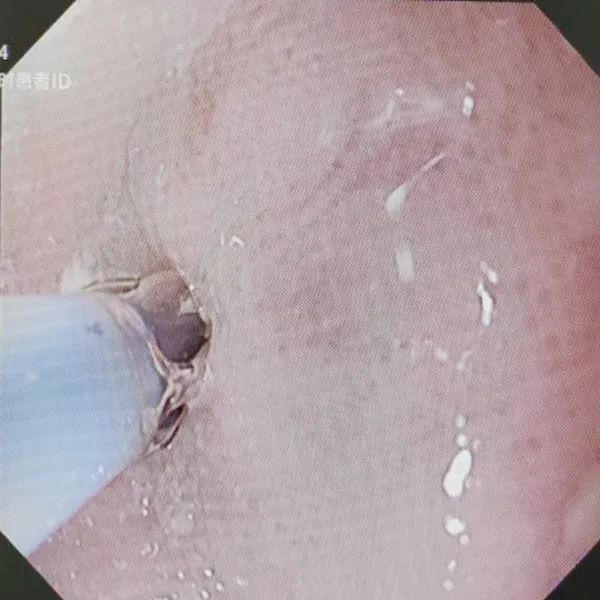

▲球囊扩张治疗中

两年前赖阿姨因腐蚀性食管炎造成食管狭窄,曾置入食管覆膜支架,但近期吞咽困难加重,吃流食也很难下咽,吃一顿稀饭需近一个小时,消化内科郑中文主任为该患者进行胃镜检查,发现进镜距门齿28-29厘米处食管腔呈环形向心性狭窄,直径仅约3-4毫米,内镜无法通过。经过综合评估,决定为其行内镜下球囊扩术。手术过程中,通过内镜活检钳道送入球囊扩张导管至狭窄段,注入生理盐水使球囊扩张,以4-8ATM(1ATM=101.325 kPa)的压力分次加压扩张,每次持续约1-2分钟,逐渐扩张狭窄食道。术后患者吞咽困难症状明显改善,无明显并发症表现,已于近日康复出院。